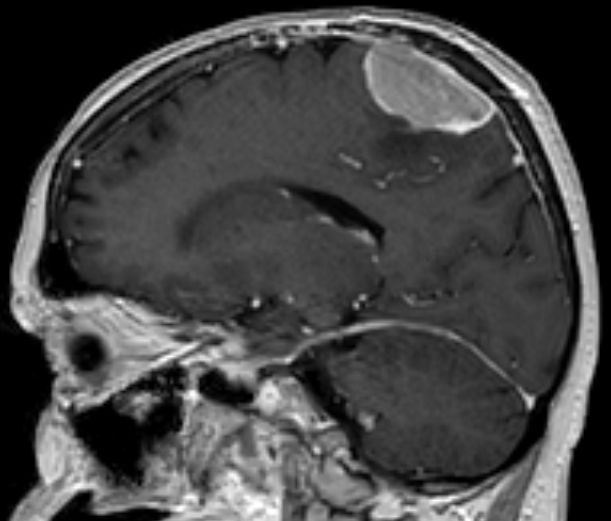

| MRT eines Meningeoms des Tentoriums |

| 72-jährige Patientin mit Teilparese des rechten Beins, passageren Sprachstörungen und Krampfanfall vor 6 Monaten. Postoperative Histologie: Meningeom Grad 1 | CT vor KM-Gabe . |

CT nach KM-Gabe . | |||||